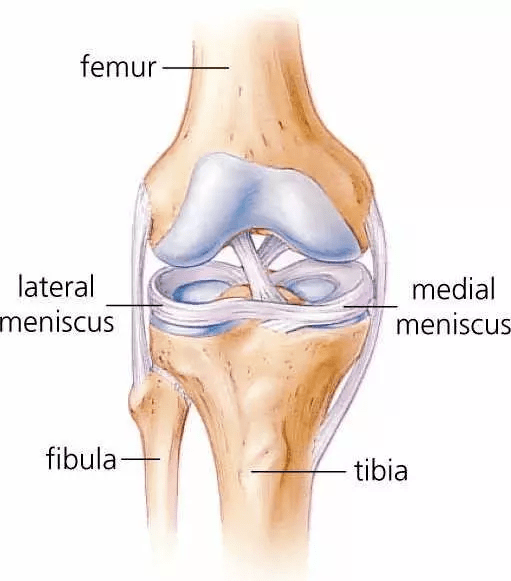

Each of your knees has two C-shaped pieces of cartilage which act like a cushion between your shinbone and your femur otherwise known as menisci. A torn meniscus causes pain, inflammation and solidness. You also may feel a block to knee motion and have trouble stretching your knee fully.

- X-rays – Because a torn meniscus is made of cartilage, it would not show up on X-rays. But X-rays could help rule out other problems with the knee which cause similar symptoms.

- MRI – This uses radio waves and a strong magnetic field to produce detailed pictures of both hard and soft tissues within your knee. It is the best imaging study to detect a torn meniscus.